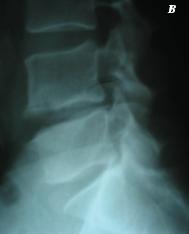

Še pred rojstvom lahko pride do motenj v zapiranju nevralnega loka vretenc, kar povzroči različne oblike hrbteničnega dizrafizma. Prav tako lahko še pred rojstvom pride do motenj v segmentaciji vretenc, kar lahko povzroča npr. prirojeno nepravilno ukrivljenost hrbtenice (skoliozo). V mladosti lahko pride do nepravilnega zraščanja nevralnega loka vretenca z ostalim delom vretenca (spondiloliza), kar lahko vodi v zdrs sprednjega dela prizadetega vretenca in celotnega hrbteničnega stebra nad njim navspred (spondilolisteza). Preobremenitve še rastoče hrbtenice lahko motijo zakostenevanje teles vretenc in povzročijo njihovo klinasto obliko, kar vodi v nepravilno obliko krivin hrbtenice (kifozo). V zrelem življenskem obdobju so poškodbe kostnih struktur hrbtenice (zlomi) pogoste v prometnih nezgodah, padcih z višine in skokih v vodo, ne da bi se poprej prepričali o njeni globini. S starostjo pride do izgube čvrstosti kostnine (osteoporoza) vretenc in s tem do zlomov, ki nastanejo že ob delovanju manjših sil, npr. dvigu lažjega bremena (slika 2). Hrbtenico lahko prizadenejo tudi različni primarno kostni ali zasevki drugotnih tumorjev (metastaze) in vnetja (spondilodiscitis).

Slika 2: Rentgenogram ledvene hrbtenice v stranski projekciji. Jasni znaki osteoporoze z zlomi teles vretenc pri 65-letni ženski